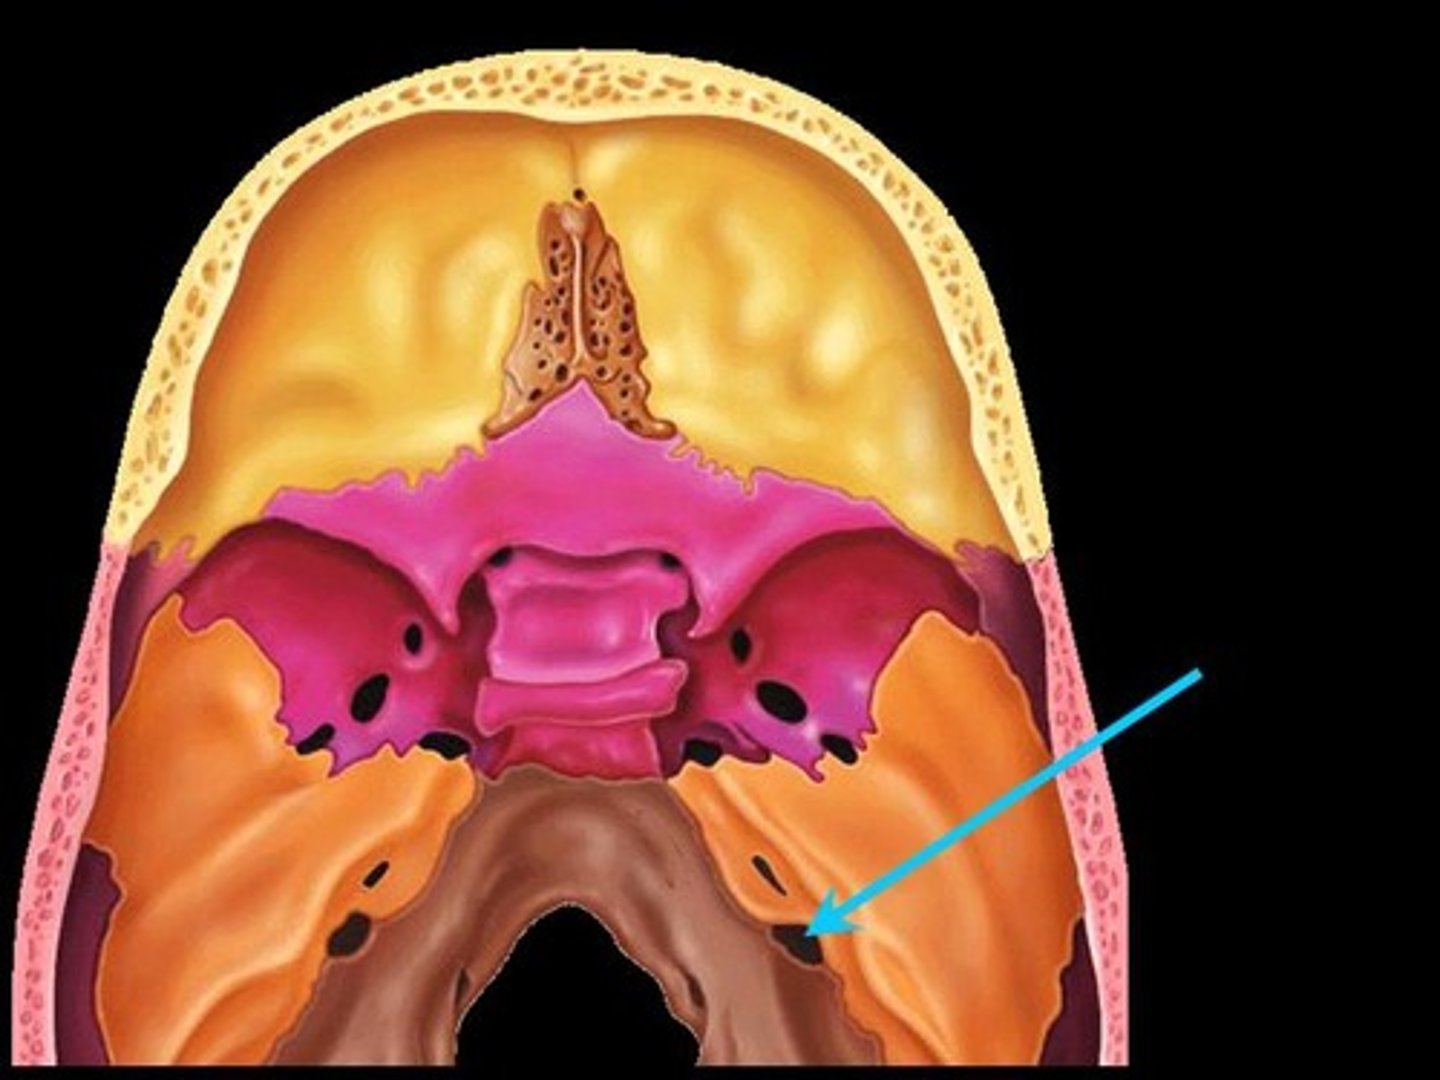

anterior cranial fossa

middle cranial fossa

posterior cranial fossa

clivus

foramen magnum

jugular foramen